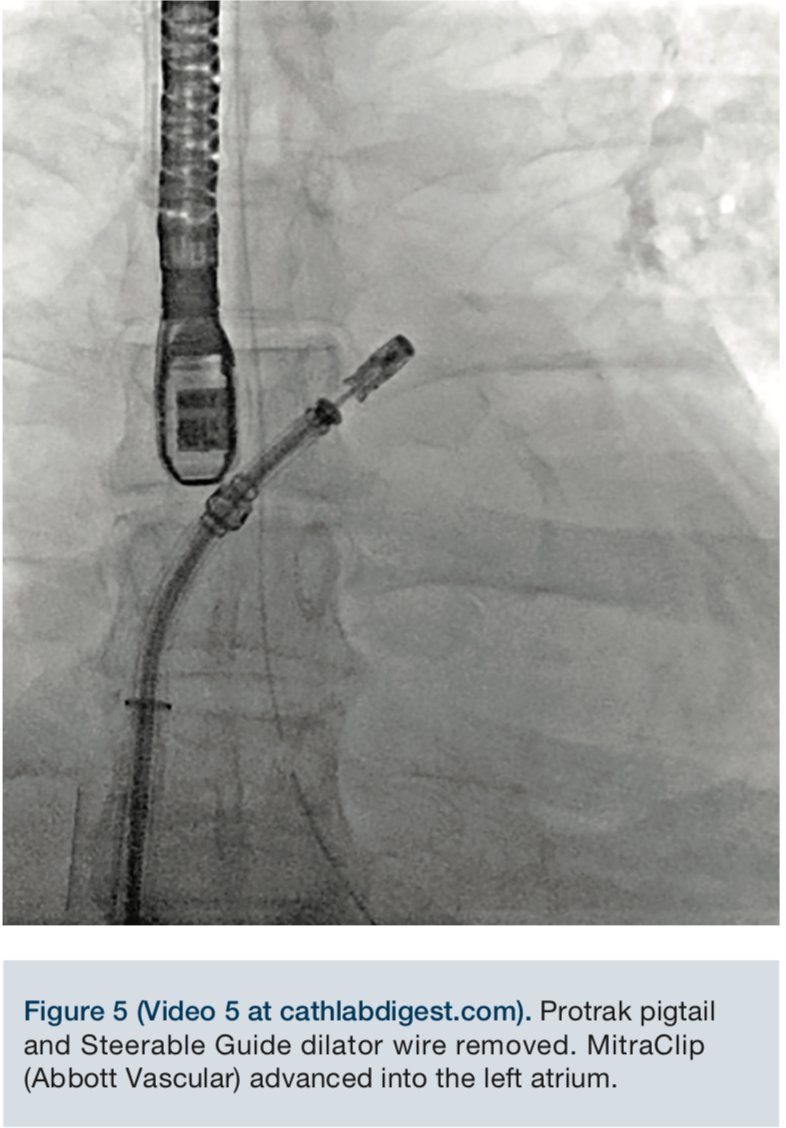

The MitraClip delivery system was then advanced into the left atrium, and the delivery system was placed into a suitable position over the targeted area, under fluoroscopic and echocardiographic guidance. The clip was advanced into the left ventricle and retracted, trapping the leaflets. The mitral regurgitation was evaluated with the clip partially closed and found to be significantly reduced. The regurgitation was essentially eliminated, and the clip was fully closed.